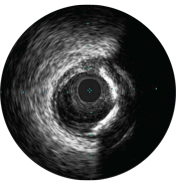

Malapposition is identified by blood behind the stent struts. ChromaFlo imaging colors blood flow red for easy recognition of malapposition and other lumen features.